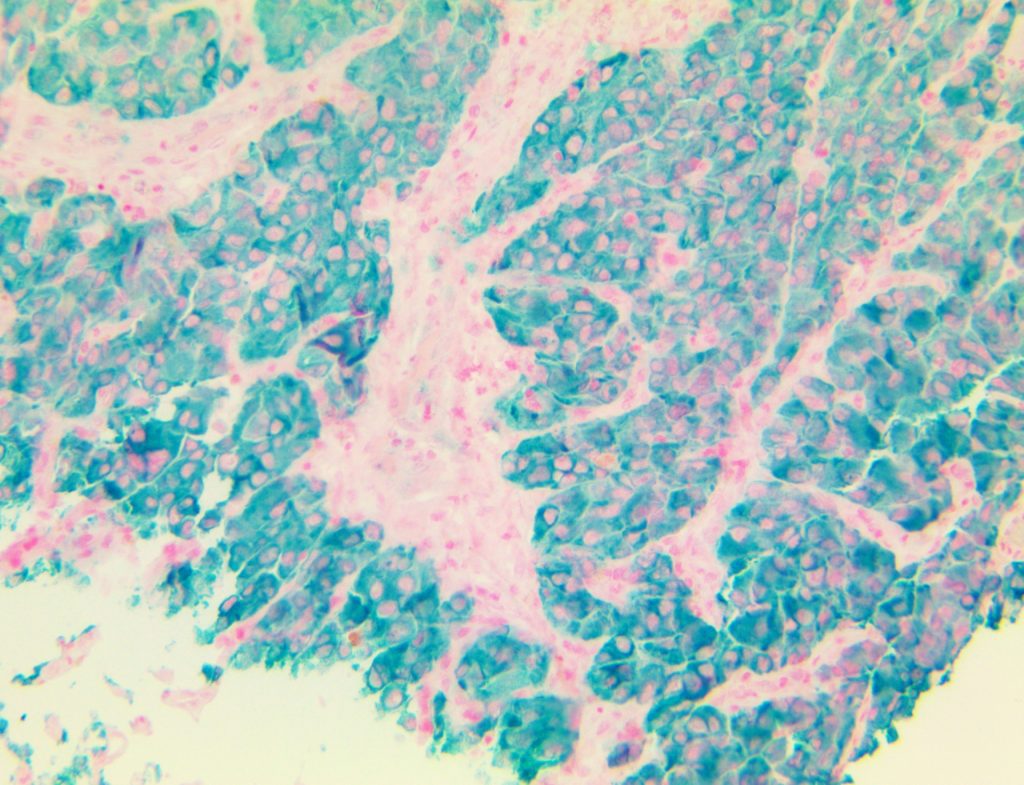

Bio SB has developed high affinity IVD monoclonal antibodies for fast immunohistochemistry (IHC) detection of melanoma, basal cell carcinoma (BCC), squamous cell carcinoma (SCC) and other Mohs surgery related conditions. Combined with our innovative IHC detection systems, we are opening the doors to a faster and more accurate immunohistochemistry applicable to Mohs surgery.

Bio SB has developed a fast, non-biotin monovalent Fab micropolymer IHC detection system for the detection of IVD antibodies for melanoma, BCC, SCC and other Mohs surgery related conditions. Our innovative IHC detection systems have opened the doors for a faster and accurate immunohistochemistry applicable to Mohs surgery.